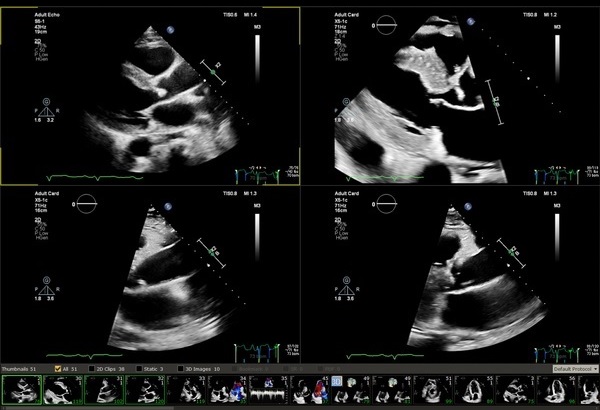

エコビューアを使用することで、超音波診断装置上で計測したDICOMストラクチャードレポートの情報のレポート取得や再計測、解析ソフトウェアが使用可能なため、検査の後でも超音波画像診断装置を占有せずに計測、解析を行うことができます。

フィリップスの超音波診断装置に適応可能な解析ソフトウェアQLABをご提供可能です。

エコー装置とほぼ同等な計測機能(Mモード、2Dモード、ドプラ)を提供します。